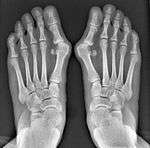

Surgical principle and technique of the syndesmosis procedure

Syndesmosis procedure addresses specifically the two fundamental problems of metatarsus primus varus deformity that gives rise to the bunion deformity. They are leaning and instability of the first metatarsal bone . Syndesmosis procedure uprights the leaning first metatarsal bone with strong binding sutures between it and the second metatarsal bone (Fig. 2) and then also stabilizes it uniquely by creating a fibrous connecting bridge between these two bones (Fig. 3,4). First metatarsal bone can be readily realigned is because by definition of the metatarsus primus varus deformity its first metatarsal is abnormally loose and mobile.

Capability and Versatility of Syndesmosis procedure

- For severe bunion deformity correction (Fig. 7)